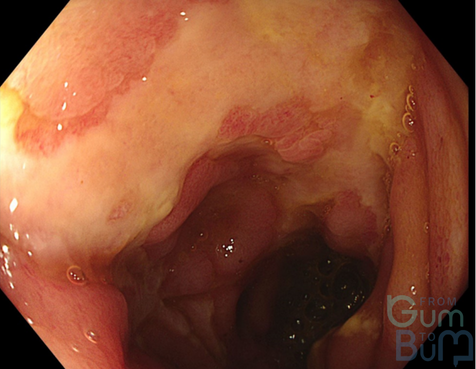

16 yo male attended with worsening RIF pain and guarding.  He reports having asthenia and weight loss over the last month.  He has not had diarrhoea.  His CRP is 110mg/l,  Hb is 10.2mgdl and white cells are 13000.

In view of suspicion of inflammatory process, a CT scan is done after a negative abdomen US for appendicitis.  CT confirms terminal ileitis confined to about 4cm of distal ileum.   Colonoscopy is performed with the attached image in the ileum, being the rest of the colonic mucosa and perianal area normal.